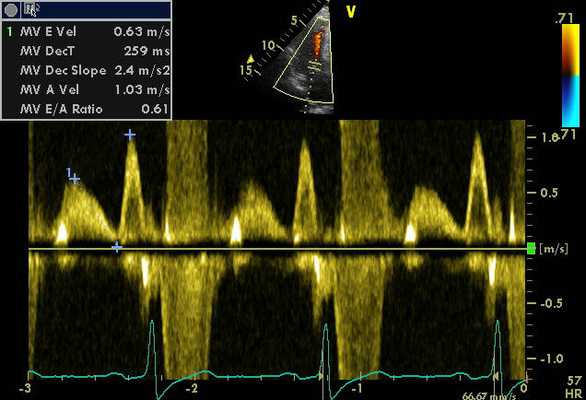

- Основные допплерографические характеристики трансмитрального и транстрикуспидального диастолического потока

- AT (acceleration time) - время ускорения потока, т.е. время от щелчка открытия клапана до пика скорости потока (м\с)

- DT (deceleration time) - время замедления потока, т.е. время от пика скорости до базовой линии (м\с)

- ЕТ (ejection time) - время выброса, т.е. время от щелчка открытия до щелчка закрытия клапана

- Vmax- максимальная скорость потока (м\с)

- Е - раннее диастолическое наполнение (Vmax = 70-100 см\с)

- А - позднее диастолическое наполнение (в момент систолы предсердий, Vmax = 40-70 см\сек)

- Е\А = 1,0-1,5

- Vmean - средняя скорость потока. Вычисляется как сумма скоростей потока, измеренных каждые 2 мс по отношению к числу измерений.

- Основные измерения в допплер эхокардиографическом исследовании

- IVCT (isovolumetric contractility time) время изоволюметрического сокращения - время от щелчка закрытия митрального клапана до щелчка открытия аортального клапана (65±20 мс)

- IVRT (isovolumetric relaxation time) время изоволюметрического расслабления - время от щелчка закрытия аортального клапана до щелчка открытия митрального клапана (65±20 мс). VTI (velocity time integral) - интеграл линейной скорости потока; VTI = Vmean*ET (см)